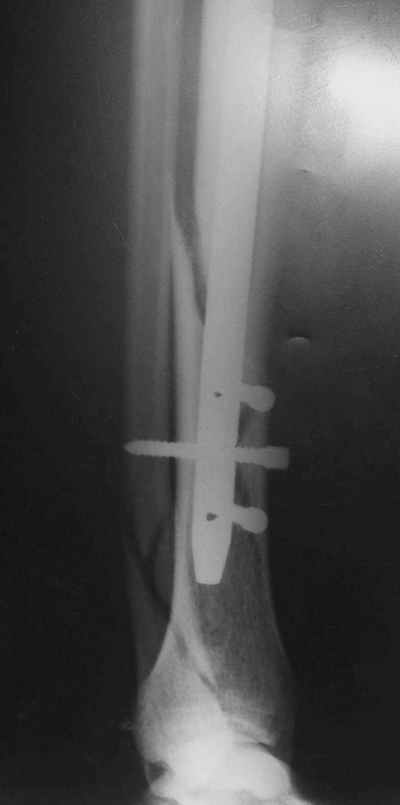

Потекли дистальные винты!

В дистальном отломке три винта( два медио-латеральных и один вентро-дорзальный).

Медио-латеральные вынты - мимо блокирующих отверстий фиксатора, вентро -

дорзальный винт - в отверстии.

Проблемы с верхним дистальным медио - латеральным винтом - он в линии перелома (

перелом косой).

То есть в дистальном отломке всего один запирающий винт. Маловато.

Если в проксимальный отломок стержень сел туго, это не мешает дистальному (широкому и короткому, раз дистальное отверстие уже на уровне перелома) быть нестабильным, особенно если он фиксирован лишь одним винтом.